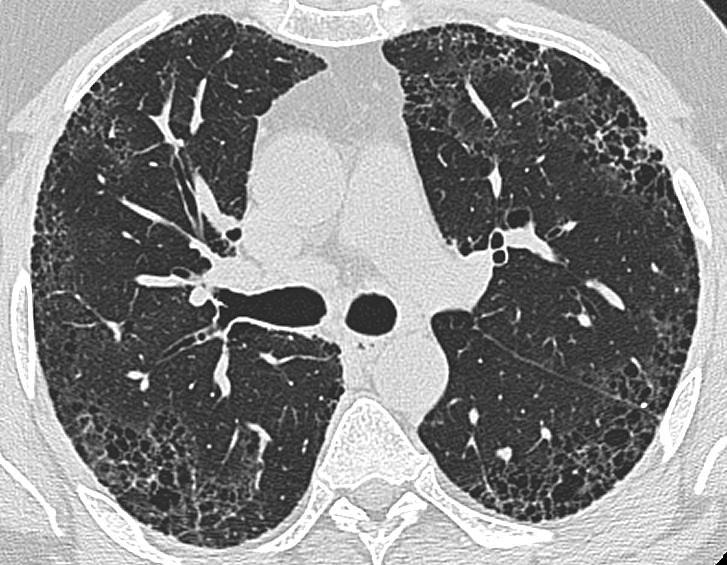

肺纤维化是以成纤维细胞增殖及大量细胞外基质聚集并伴炎症损伤、组织结构破坏为特征的一大类肺疾病的终末期改变,也就是正常的肺泡组织被损坏后经过异常修复导致结构异常(疤痕形成)。绝大部分肺纤维化病人病因不明(特发性),这组疾病称为特发性间质性肺炎(IIP),是间质性肺病中一大类。而特发性间质性肺炎(IIP)中最常见的以肺纤维化病变为主要表现形式的疾病类型为特发性肺更多>>